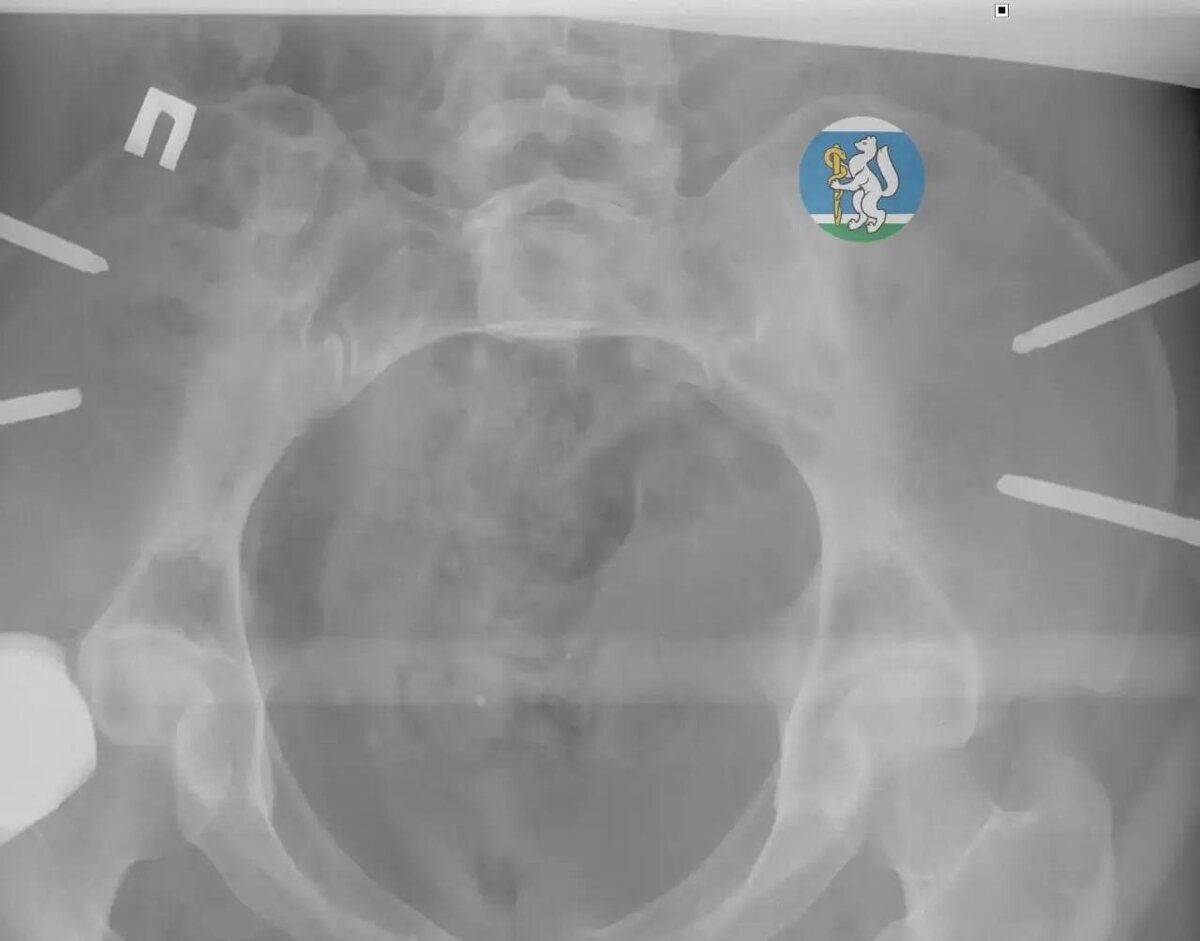

36-лСтняя ΠΆΠΈΡ‚Π΅Π»ΡŒΠ½ΠΈΡ†Π° Π•ΠΊΠ°Ρ‚Π΅Ρ€ΠΈΠ½Π±ΡƒΡ€Π³Π° ΡƒΠΏΠ°Π»Π° с сСдьмого этаТа, ΠΊΠΎΠ³Π΄Π° ΠΌΡ‹Π»Π° ΠΎΠΊΠ½Π°. Π’ состоянии Ρ‚ΡΠΆΠ΅Π»Π΅ΠΉΡˆΠ΅Π³ΠΎ травматичСского шока Π΅Ρ‘ доставили Π² Π“ΠΎΡ€ΠΎΠ΄ΡΠΊΡƒΡŽ Π±ΠΎΠ»ΡŒΠ½ΠΈΡ†Ρƒ β„–36 «ВравматологичСская», Π³Π΄Π΅ Π²Ρ€Π°Ρ‡ΠΈ диагностировали Ρ‡Π΅Ρ€Π΅ΠΏΠ½ΠΎ-ΠΌΠΎΠ·Π³ΠΎΠ²ΡƒΡŽ Ρ‚Ρ€Π°Π²ΠΌΡƒ, ΠΏΠΎΠ²Ρ€Π΅ΠΆΠ΄Π΅Π½ΠΈΠ΅ ΠΏΠΎΠ·Π²ΠΎΠ½ΠΎΡ‡Π½ΠΈΠΊΠ°, мноТСствСнныС ΠΏΠ΅Ρ€Π΅Π»ΠΎΠΌΡ‹ Ρ‚Π°Π·Π° ΠΈ ΠΎΡ‚ΠΊΡ€Ρ‹Ρ‚Ρ‹Π΅ ΠΏΠ΅Ρ€Π΅Π»ΠΎΠΌΡ‹ Π½ΠΎΠ³ΠΈ. Π‘ΠΎΠ»ΡŒΡˆΠΈΠ½ΡΡ‚Π²ΠΎ ΠΏΠΎΡΡ‚Ρ€Π°Π΄Π°Π²ΡˆΠΈΡ… с Ρ‚Π°ΠΊΠΈΠΌΠΈ Ρ‚Ρ€Π°Π²ΠΌΠ°ΠΌΠΈ Π½Π΅ Π΄ΠΎΠΆΠΈΠ²Π°ΡŽΡ‚ Π΄ΠΎ ΠΏΡ€ΠΈΠ΅Π·Π΄Π° скорой.

πŸ§‘ НСсколько часов Π±Ρ€ΠΈΠ³Π°Π΄Π° Ρ…ΠΈΡ€ΡƒΡ€Π³ΠΎΠ², Ρ‚Ρ€Π°Π²ΠΌΠ°Ρ‚ΠΎΠ»ΠΎΠ³ΠΎΠ², Π½Π΅ΠΉΡ€ΠΎΡ…ΠΈΡ€ΡƒΡ€Π³Π° ΠΈ Ρ€Π΅Π°Π½ΠΈΠΌΠ°Ρ‚ΠΎΠ»ΠΎΠ³Π° Π±ΡƒΠΊΠ²Π°Π»ΡŒΠ½ΠΎ Π²Ρ‹Ρ€Ρ‹Π²Π°Π»Π° ΠΆΠ΅Π½Ρ‰ΠΈΠ½Ρƒ с Ρ‚ΠΎΠ³ΠΎ свСта. Π Π°Π±ΠΎΡ‚Π° шла поэтапно: сначала рСанимация, Π·Π°Ρ‚Π΅ΠΌ стабилизация, ΠΏΠΎΡ‚ΠΎΠΌ β€” сСрия ΠΎΠΏΠ΅Ρ€Π°Ρ†ΠΈΠΉ. Бпустя мСсяц ΠΏΠ°Ρ†ΠΈΠ΅Π½Ρ‚ΠΊΡƒ выписали Π² ΡƒΠ΄ΠΎΠ²Π»Π΅Ρ‚Π²ΠΎΡ€ΠΈΡ‚Π΅Π»ΡŒΠ½ΠΎΠΌ состоянии, ΠΈ сСгодня ΠΎΠ½Π° ΠΏΡ€ΠΎΡ…ΠΎΠ΄ΠΈΡ‚ Ρ€Π΅Π°Π±ΠΈΠ»ΠΈΡ‚Π°Ρ†ΠΈΡŽ.